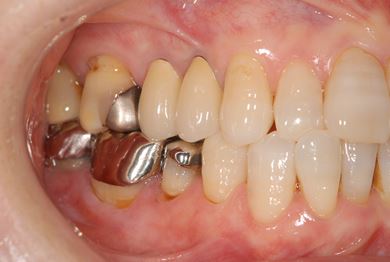

インプラント治療+セラミック治療

| カテゴリー | 【インプラント治療】【セラミック治療】 | ||||||||||||||||||||||||||||||||

| 性別/年齢 | 女性 / 61歳 | ||||||||||||||||||||||||||||||||

| 主訴 | 奥歯がぐらつく。 | ||||||||||||||||||||||||||||||||

| 治療方針 | インプラント治療にて機能的・審美的回復を行う。 | ||||||||||||||||||||||||||||||||

| 治療内容 | インプラント1本、メタルボンドセラミッククラウン3本(メタルボンドセラミック用土台2本) | ||||||||||||||||||||||||||||||||

| 総治療費 | 625,538円 | ||||||||||||||||||||||||||||||||

| 治療期間 | 1年0ヶ月 |